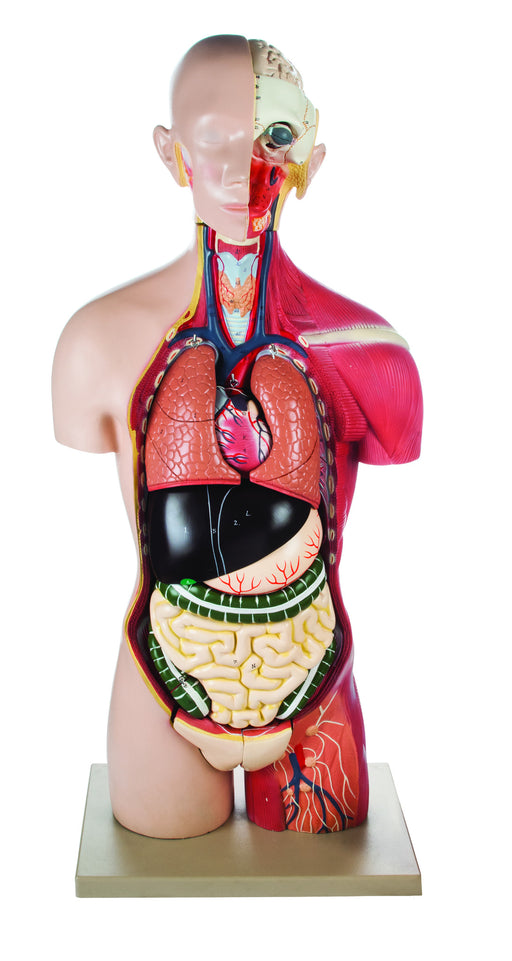

Full Muscle Torso with Dual Sex Organs and Open Back Ÿ?? 24 Parts

The detailed, life size 3D rendering of the human torso with its vibrantly colored anatomy is ideal for studying the structure and function of the ...

View full detailsAM16003 -